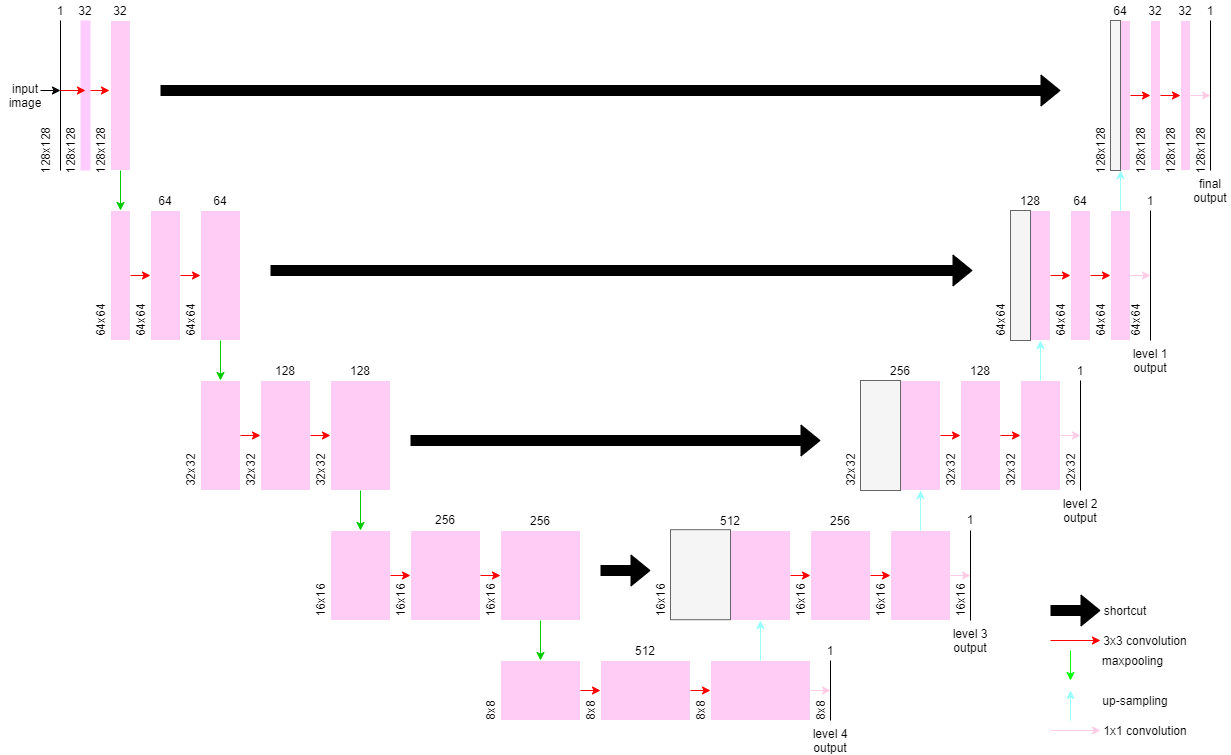

We have applied deep supervision on both U-Net and MultiResUNet models. Rather than only evaluating the output of the top layer’s decoder, this model associates loss weights with the outputs of all five layers, in descending order from top to bottom. In order to achieve this, a simple 1 x 1 convolution is applied in all the layers after the up-Sampling and convolution operations. Figure 3 presents Deeply Supervised U-Net and MultiResUNet models.

(a) Deeply Supervised U-Net

(b) Deeply Supervised MultiResUNet Figure 3: Deeply Supervised Networks